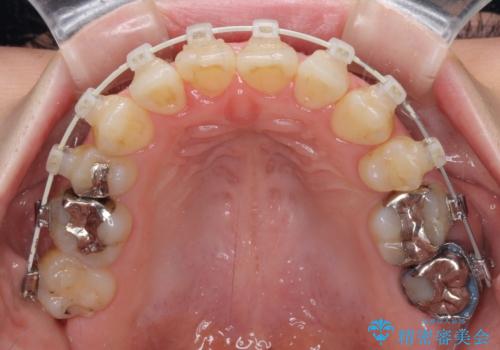

- 審美装置

口元の突出感とデコボコがあり、上下左右の小臼歯4本を抜歯して矯正治療を行う方針としました。(右上は欠損のため計3本抜歯)

むし歯となっている歯は状態が悪く、将来的に抜歯となる可能性が高かったため、定石で抜歯させる小臼歯の代わりにむし歯となっている大臼歯を抜歯し、ワイヤー装置にて矯正治療を行うこととしました。

イレギュラーな大臼歯抜歯矯正であったため、治療期間の長期化が想定されましたが、何とか3年ちょうどで終えることができました。